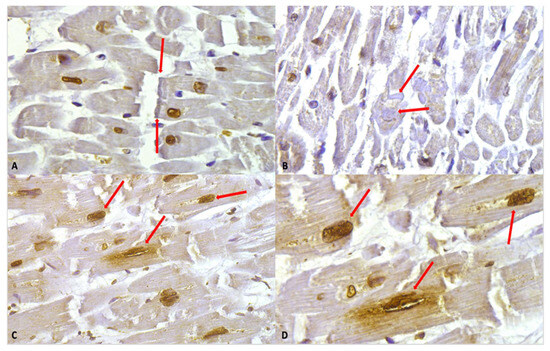

Despite the intensity of the staining, in the study group, we observed hypercontracted myocardial cells with rhexis of the myofibrillar apparatus into cross-fibre, anomalous, and irregular bands (contraction band necrosis, CBN). The necrosis was multifocal and formed by foci of a few cells; a myofibrillar rhexis with evidence of doubling of the rupture extremity, indicating that the rupture occurred at the site of a contraction band (Figure 4).

Figure 4.

(A) Myofibrillar rhexis with doubling of the rupture extremity (red arrows). Cardiomyocytes nuclei immunostaining is shown, along with a slight positivity in myofibers. (B) Contraction bands (red arrows) in the context of myofiber moderate positivity immunostaining. (C) Nuclear and perinuclear positive immunostaining (red arrows) 40×. (D) Clearly visible at higher magnification, the nuclear and perinuclear positive (red arrows) immunostaining, 60×.